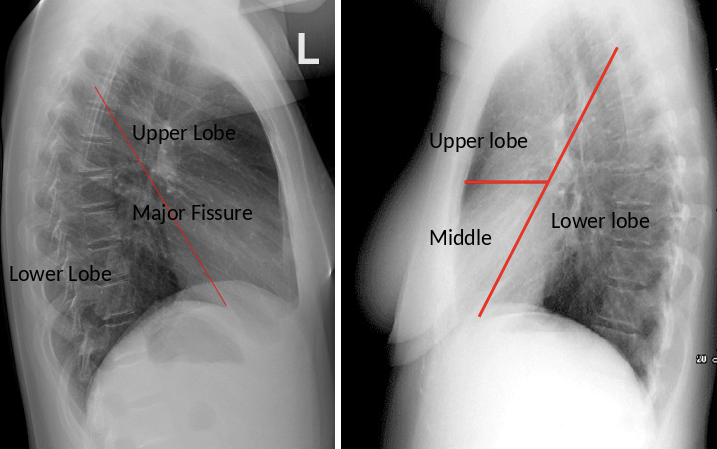

Fissures and lobes